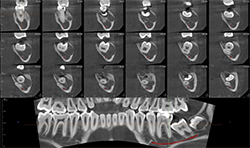

Case 4: 59-year-old woman with pain and sinus tract associated with endodontically treated #14

Periapical radiographs (Figs. 8A, 8B) show that radiolucent area around the mesial root of #14 and missing lamina dura. The apical lesion is close to the floor of the left maxillary sinus.

CBCT (Figs. 9A, 9B) reveals the lesion extends from the buccal cortex to the palatal cortex with furcation involvement and involves the palatal root. Mucosal thickening is noted along the floor of the left maxillary sinus, suggesting odontogenic origin. Tooth extraction would be recommended.